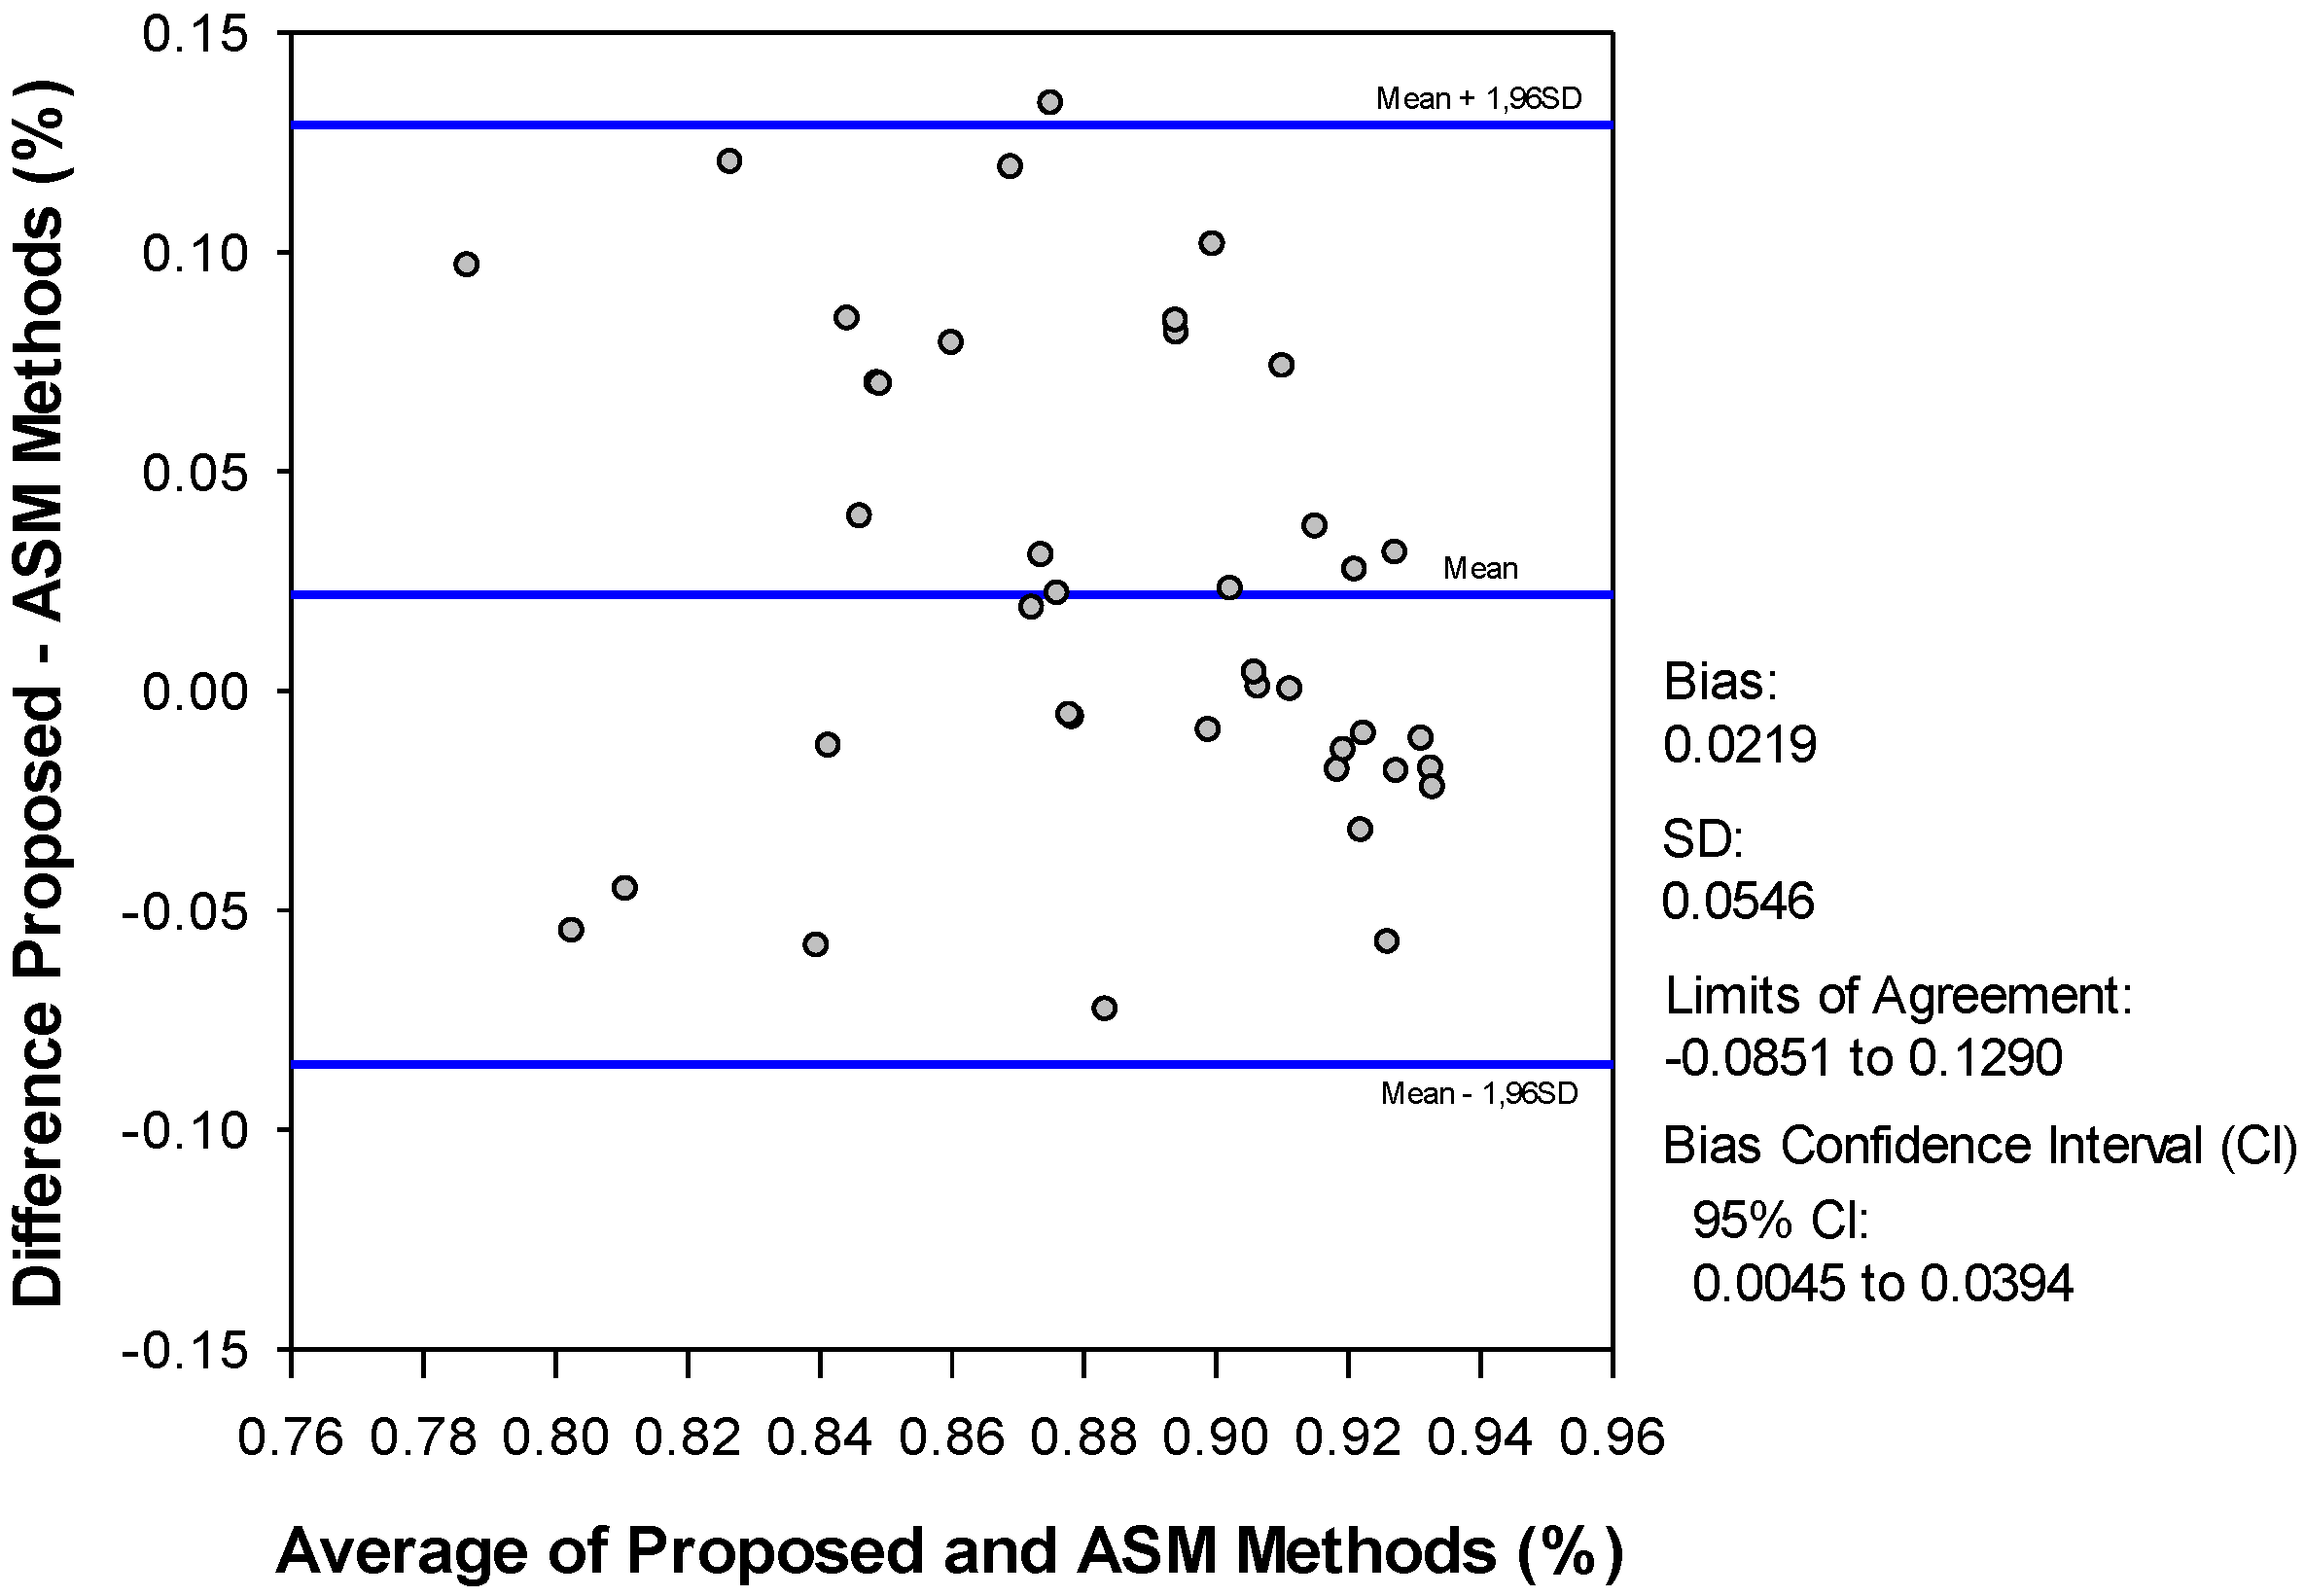

4. Discussion